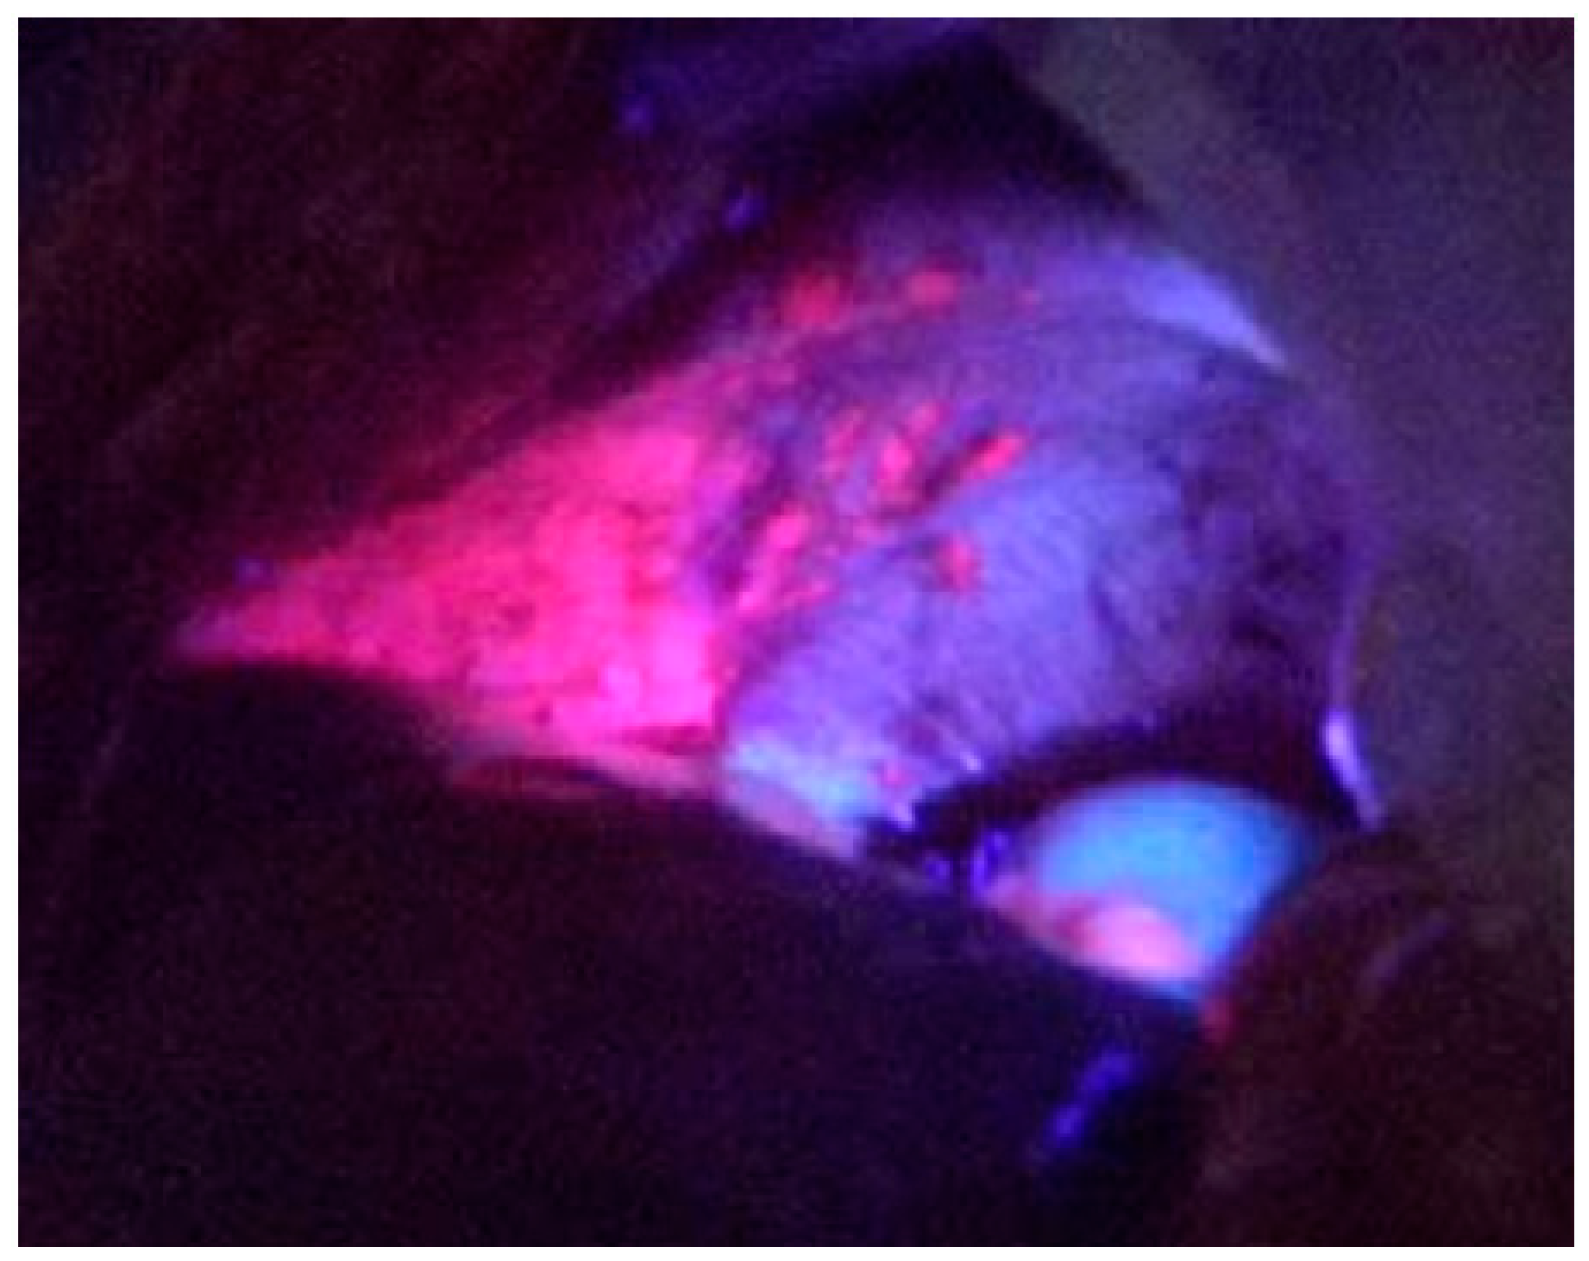

3.2. ALA PDD in Experimental PM

- Yonemura, Y.; Canbay, E.; Ishibashi, H.; Nishino, E.; Endou, Y.; Sako, S.; Ogura, S. 5-aminolevulinic acid fluorescence in detection of peritoneal metastases. Asian Pac. J. Cancer Prev. 2016, 17, 2271–2275. [Google Scholar] [CrossRef] [PubMed]

- Yonemura, Y.; Ishibashi, H.; Sako, S. ALA fluorescence guided surgery. In Comprehensive Treatment for Peritoneal Surface Malignancy with an Intent of Cure; Yonemura, Y., Ed.; Asian School of Peritoneal Surface Oncology: Osaka, Japan, 2014; pp. 110–117. [Google Scholar]

- Löning, M.; Diddens, H.; Küpker, W.; Diedrich, K.; Hüttmann, G. Laparoscopic fluorescent detection of ovarian carcinoma metastasis using 5-aminolevulinic acid-induced protoporphyrin IX. Cancer 2004, 100, 1650–1656. [Google Scholar] [CrossRef] [PubMed]

- Canis, M.; Botchorishvili, R.; Berreni, N.; Manhes, H.; Wattiez, A.; Mage, G.; Pouly, J.L.; Bruhat, M.A. 5-amininolevulinic acid-induced (ALA) fluorescence for the laparoscopic diagnosis of peritoneal metastasis. An experimental study. Sur. Endoscopy. 2001, 15, 1184–1186. [Google Scholar] [CrossRef] [PubMed]

- Gahlen, J.; Pietschmann, M.; Prosst, R.L.; Herfarth, C. Systemic vs local administration of delta-aminolevulinic acid for laparoscopic fluorescence diagnosis of malignant intra-abdominal tumors-Experimental study. Surg. Endoscopy. 2001, 15, 196–199. [Google Scholar] [CrossRef]

- Hornung, R.; Major, A.L.; McHale, M.; Liaw, L.H.; Sabiniano, L.A.; Tromberg, B.J.; Berns, M.W.; Tadir, Y. In vivo detection of metastatic ovarian cancer by means of 5-aminolevulinic acid-Induced fluorescence in a rat model. J. Am. Assoc. Gynecol. Laparoscopist. 1998, 5, 141–148. [Google Scholar] [CrossRef]

- Lüdicke, F.; Gabrecht, T.; Lange, N.; Wagnières, G.; van Den Bergh, H.; Berclaz, L.; Major, A.L. Photodynamic diagnosis of ovarian cancer using hexaminolevulinate: A preclinical study. Br. J. Cancer. 2003, 88, 1780–1784. [Google Scholar] [CrossRef] [PubMed][Green Version]

- Murayama, Y.; Ichikawa, D.; Koizumi, N.; Komatsu, S.; Shiozaki, A.; Kuriu, Y.; Ikoma, H.; Kubota, T.; Nakanishi, M.; Harada, Y.; et al. Staging fluorescence laparoscopy for gastric cancer by using 5-aminolevulinic acid. Anticancer Res. 2012, 32, 5421–5427. [Google Scholar] [PubMed]